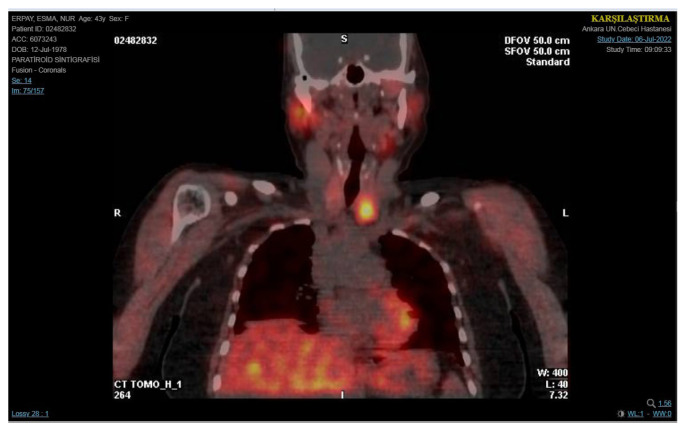

Materials and methods: A 45-year-old woman who had previously experienced high levels of calcium in her blood and abnormally elevated parathyroid hormone levels underwent surgical removal of the left parathyroid gland. Following surgery, she exhibited high levels of parathyroid hormone along with normalized calcium levels and persistent fatigue. Ultrasound imaging showed a hypoechoic mass on the left side, which was initially considered to be a recurrent parathyroid tumor.

Results: A comprehensive assessment, including neck CT scans and fine needle aspiration cytology, revealed that the mass was actually residual surgical cellulose, making diagnosis more challenging due to vitamin D deficiency.